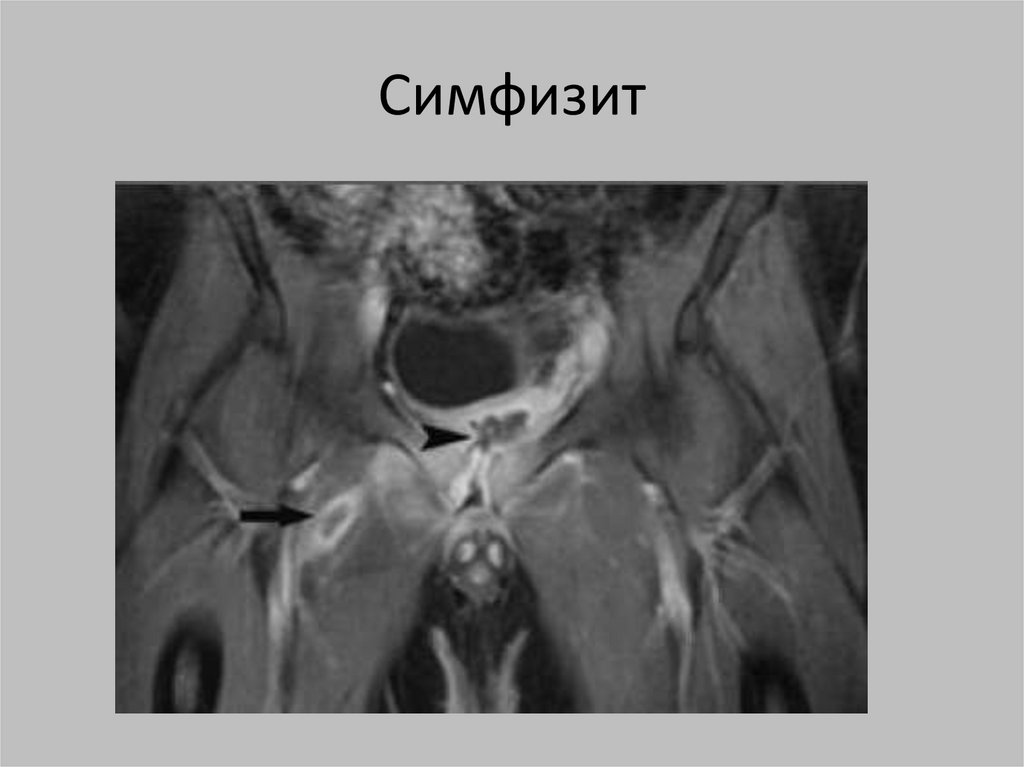

Симфизит